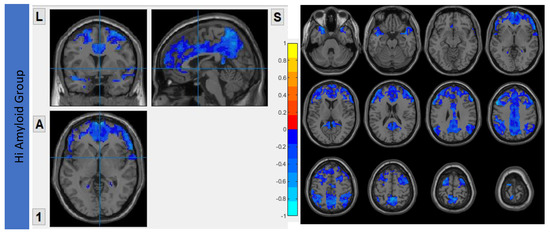

The VMHC maps for the HiAmy and LowAmy groups when compared to HC were showed in Figure 2. For the HiAmy group, the VMHC maps showed reduced functional connectivity in most regions in DMN, CEN, SRN and SMN, except in regions of salience network, including anterior insular, anterior cingulate gyrus, putamen, pallidum, caudate and amygdala. While for LowAmy group, the VMHC maps showed increased functional connectivity in the precentral gyrus, superior frontal gyrus, inferior frontal operculum, rolandic operculum, supplementary motor area, anterior insular, middle cingulate and caudate.

VMHC Maps showing interhemispheric functional connectivity (IFC) of HiAmy and LowAmy groups when compared to HC. (a) showed Voxel-wise two-sample t-tests of VMHC maps from HiAmy when compared to HC. (b) showed Voxel-wise two-sample t-tests of VMHC maps from LowAmy when compared to HC. All comparisons were adjusted for age, sex, and total intracranial volume, with Gaussian random field correction. The significance threshold at the voxel level was set at p < 0.01; and at cluster level was set at p < 0.05. The blue and red colors illustrate significant t values according to the scale on the right. VMHC: Voxel Mirrored Homotopic Connectivity. HC: Health Control. HiAmy: Patient group with global SUVr > 0.62. LowAmy: Patient group with global SUVc < 0.62.